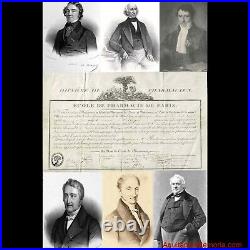

Ecole de Pharmacie de Paris (1836) : Diplôme de pharmacien 1836. La création et l’organisation de l’Ecole de Pharmacie de Paris datent de la loi du 11 avril 1803 et du décret du 8 octobre de la même année. De sa création en 1803. À son rattachement à l’Université en 1840, aucun acte législatif ou règlementaire majeur ne vient modifier la situation de l’école. En 1803 comme en 1836, date de ce document, des professeurs de l’Ecole de Médecine de Paris siègent dans les jurys d’examen. Ceci explique que ce diplôme soit délivré par les «. Professeurs à l’Ecole de Pharmacie de Paris, et Professeurs à l’école de médecine de la même Ville. Pour l’Ecole de Médecine. Médecin et chimiste espagnol, naturalisé français en 1818, il est un pionnier de la toxicologie médico-légale. Il signe ce document deux fois. La première en qualité de professeur, depuis 1819, à la faculté de médecine de Paris. La seconde comme doyen (1831 à 1848) de cette même école. Depuis 1834, il est également membre du Conseil royal de l’Instruction publique. Reçu docteur en médecine en 1820, il devint aide naturaliste au Muséum d’Histoire naturelle en 1827. En 1831, il obtient la place de professeur d’histoire naturelle médicale à la Faculté de Médecine de Paris, reprenant ainsi la fonction de son père, le botaniste Louis Claude Richard (1754 -1821). Pour l’Ecole de Pharmacie. Reçu maître en pharmacie en 1787, il s’adonne ensuite à la chimie. Attaché comme pharmacien à la maison de l’empereur, il accompagne Napoléon Ier lors de ses campagnes en Autriche et en Prusse. Lors de la fondation en 1803 de l’école de pharmacie, il occupe la chaire de chimie. En 1829, il devint directeur-adjoint et en 1832 directeur. C’est à ce poste qu’il signe ce diplôme. Pharmacien et chimiste français. Il fait d’importantes recherches sur les alcaloïdes d’origine végétale et découvre avec Joseph Caventou la quinine et la strychnine. Figure éminente de la pharmacie et de la chimie, ses recherches mettent en évidence plusieurs principes actifs comme la caféine, la narcotine et surtout la codéine. Louis René Le Canu. Il fait notamment paraître plusieurs mémoire sur le sang, sujet qui ne cesse de l’occuper pendant toute la durée de sa carrière. Document su vélin (335 x 216) avec frontispice au coq et « caducée exotique ». Diplôme délivré à Paris le 2 février 1836 et attribué à Joseph Alexandre BLANCHART. Ce dernier, né en 1812 à Péruwelz en BELGIQUE d’un père pharmacien, bénéficie d’une dispense d’âge pour ses examens. Diplôme avec un pli dans le sens de la longueur et trois dans la largeur. Les produits proposés à la vente sont de nature, de poids et de tailles très hétérogènes. Le paiement est considéré comme « soldé » une fois que l’argent envoyé par l’acheteur a été déposé sur le compte du vendeur. Paiement en ligne par carte bancaire. Par virement national ou international.